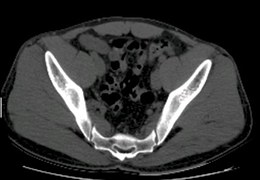

View X-Ray CT & MRI Scans Fast and Easily

Designed for surgeons, Pro Surgical 3D makes it easy to view patient scans quickly. Pro Surgical 3D facilitates the optimal 3D treatment and assessment workflows based on X-ray CT and MRI scans – and best of all, it’s FREE!

Designed mainly for CT and MR DICOM modalities.

Multi-planar slicing.